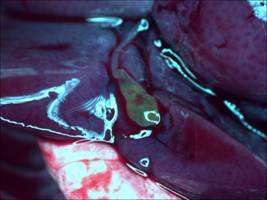

[客戶實(shí)驗(yàn)方法] 以小白鼠作為實(shí)驗(yàn)動(dòng)物模型,通過體視熒光顯微鏡觀察實(shí)驗(yàn)組和對(duì)照組,在同一參數(shù)設(shè)置下,用明美成像系統(tǒng)分析軟件將明場(chǎng)、熒光分別拍攝的效果圖合成,檢測(cè)藥物作用部位。

[實(shí)拍顯微圖片]

實(shí)驗(yàn)組:

藥物膽明場(chǎng)

藥物膽熒光